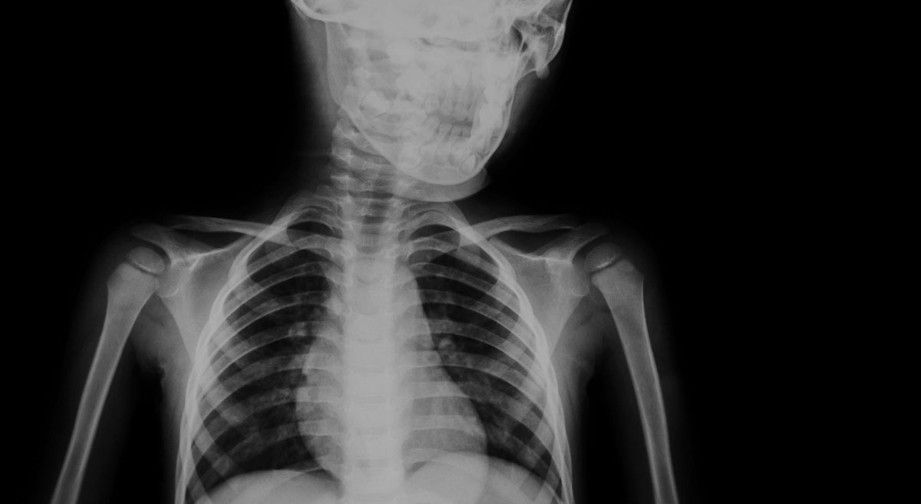

Some medical imaging procedures involve the use of ionising radiation:

- X-Rays

Extra consideration for children and pregnant women

Extra consideration is made for imaging of women of reproductive age and children. Medical imaging for these groups may still be needed and may indeed be very important, but extra care must be taken to optimise the study and ensure the benefit outweighs any potential risks.